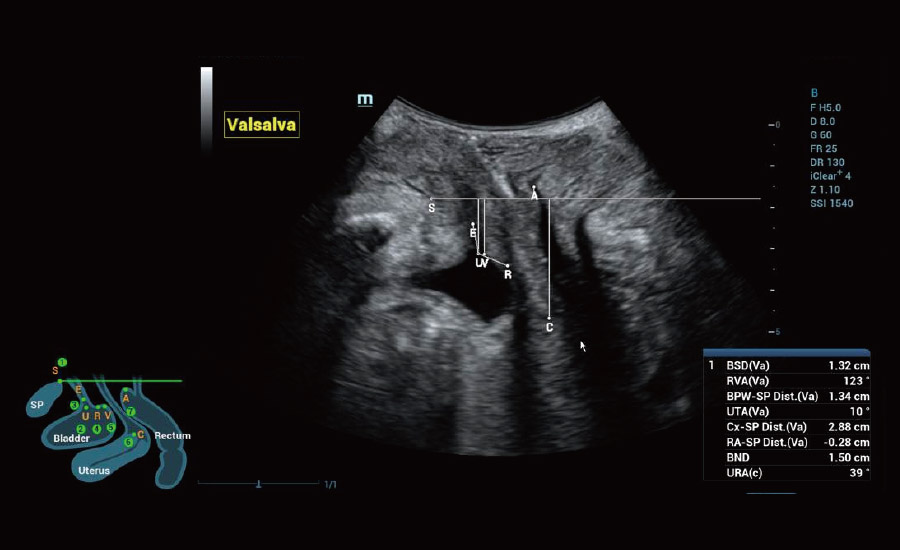

Urogynecology